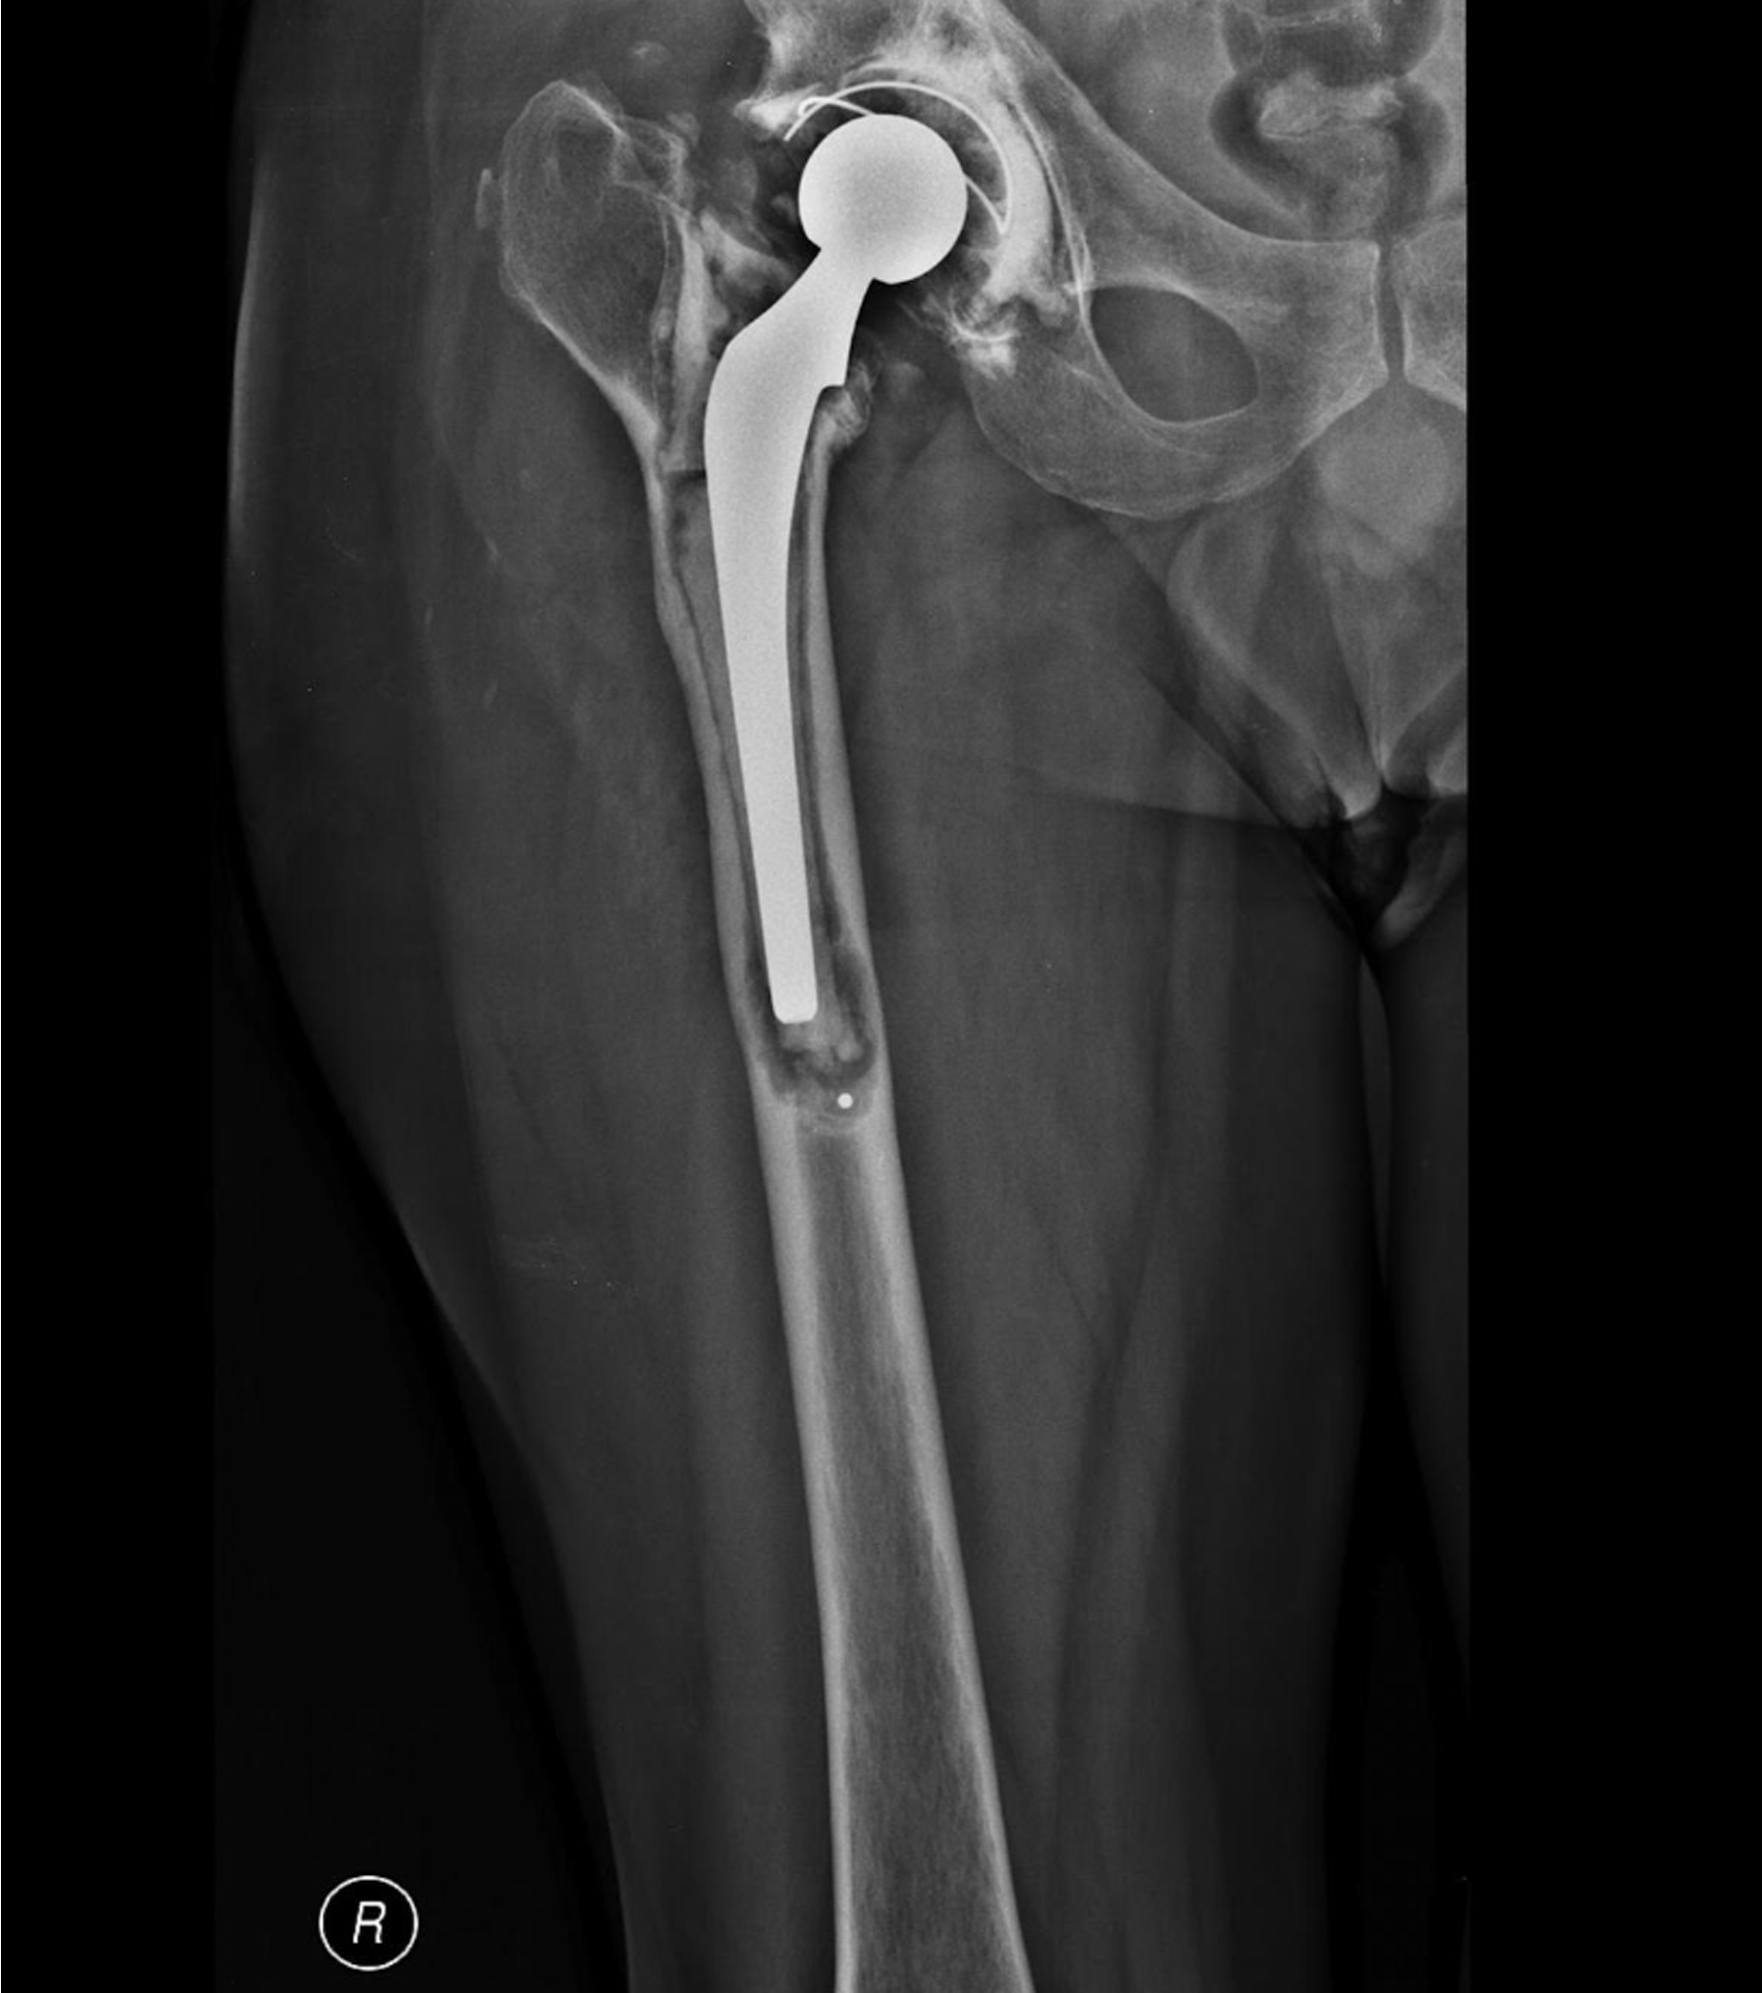

Radiograph showing aseptic loosening of the femoral component of a total hip replacement

Having had a right uncemented total hip replacement using an 8mm femoral stem, a man in his sixties required revision surgery two years later, having experienced persistent pain due to the femoral stem having become loose and fractured.

The claimant alleged that the entry point for introduction of both the rasps and prosthesis had been excessively medial, resulting in an inappropriately small prosthesis being used and implanted in varus. There was subsequent migration and aseptic loosening of the component and failure of the prosthesis.

The allegation was not accepted by the operating surgeon, who claimed he had to use the small prosthesis because of the abnormally excessive curvature of the claimant’s femur.

The case could not be defended at trial, however, as there was found to be insufficient evidence in the operation note to support the surgeon’s account. Specifically, there was a lack of detail as to the surgical approach and a lack of explanation in the operative record regarding the rationale for the unusually small prosthesis.